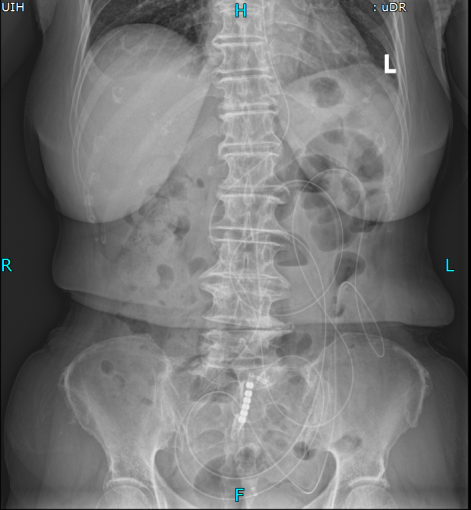

术前立位腹平片

主任医师叶晋生结合病历和CT检查结果,明确诊断:低位小肠梗阻,且王奶奶有两次腹部手术史,肠粘连概率极高,肠管随时可能因过度扩张穿孔,需要先减压再评估。